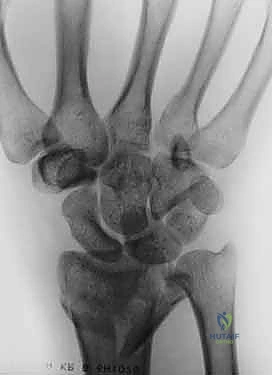

- الأشعة السينية (X-rays):

هي الخطوة الأولى لتقييم الكسر. يتم أخذ صور من زوايا متعددة (أمامية خلفية، جانبية، ومائلة) لتحديد موقع الكسر الأساسي ودرجة الانزياح والتقصير في عظم الكعبرة.

- التصوير المقطعي المحوسب (CT Scan) مع إعادة البناء ثلاثي الأبعاد:

هذا هو المعيار الذهبي الذي يعتمده الدكتور هطيف لجميع كسور المفصل المعقدة. تتيح الأشعة المقطعية رؤية كل شظية عظمية بوضوح تام، وتحديد حجمها، وموقعها، ودرجة تفتت السطح المفصلي بدقة ملليمترية. من خلال إعادة البناء ثلاثي الأبعاد (3D Reconstruction)، يمكن للدكتور هطيف "رؤية" الكسر من جميع الزوايا قبل فتح الجلد، مما يسمح له باختيار الغرسات (الصفائح والمسامير) الدقيقة لكل شظية وتحديد المداخل الجراحية المثلى.